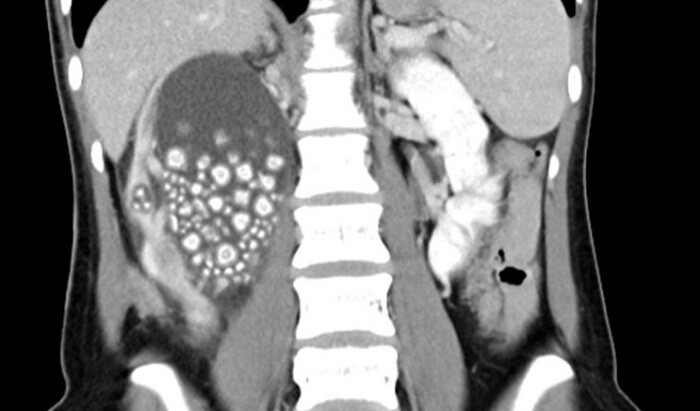

Dokter memerintahkan CT scan yang menunjukkan bahwa ginjal kanan Xiao Yu penuh dengan cairan dan hampir penuh dengan batu ginjal.

Taiwan News melaporkan, sebagian besar batu tersebut memiliki penampilan yang mirip dengan "roti kukus kecil".